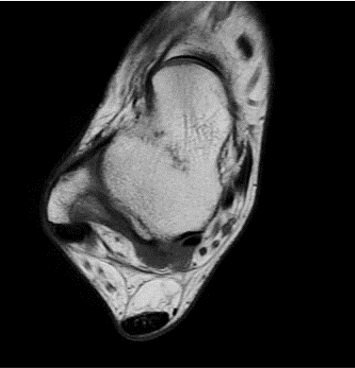

384 x 256 (2 NEX)

1:30 minstandard

384 x 256 (4 NEX)

2:59 minIAI (Innovative AI)

384 x 256 (2 NEX)

1:28 minReduced Scan Time

384 x 256 (2 NEX)

1:28 minConventional